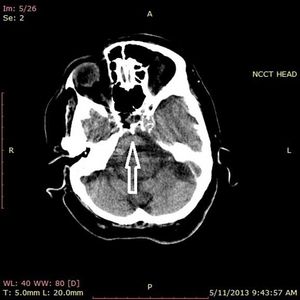

Case History: Four-year-old patient with complaints of altered sensorium.